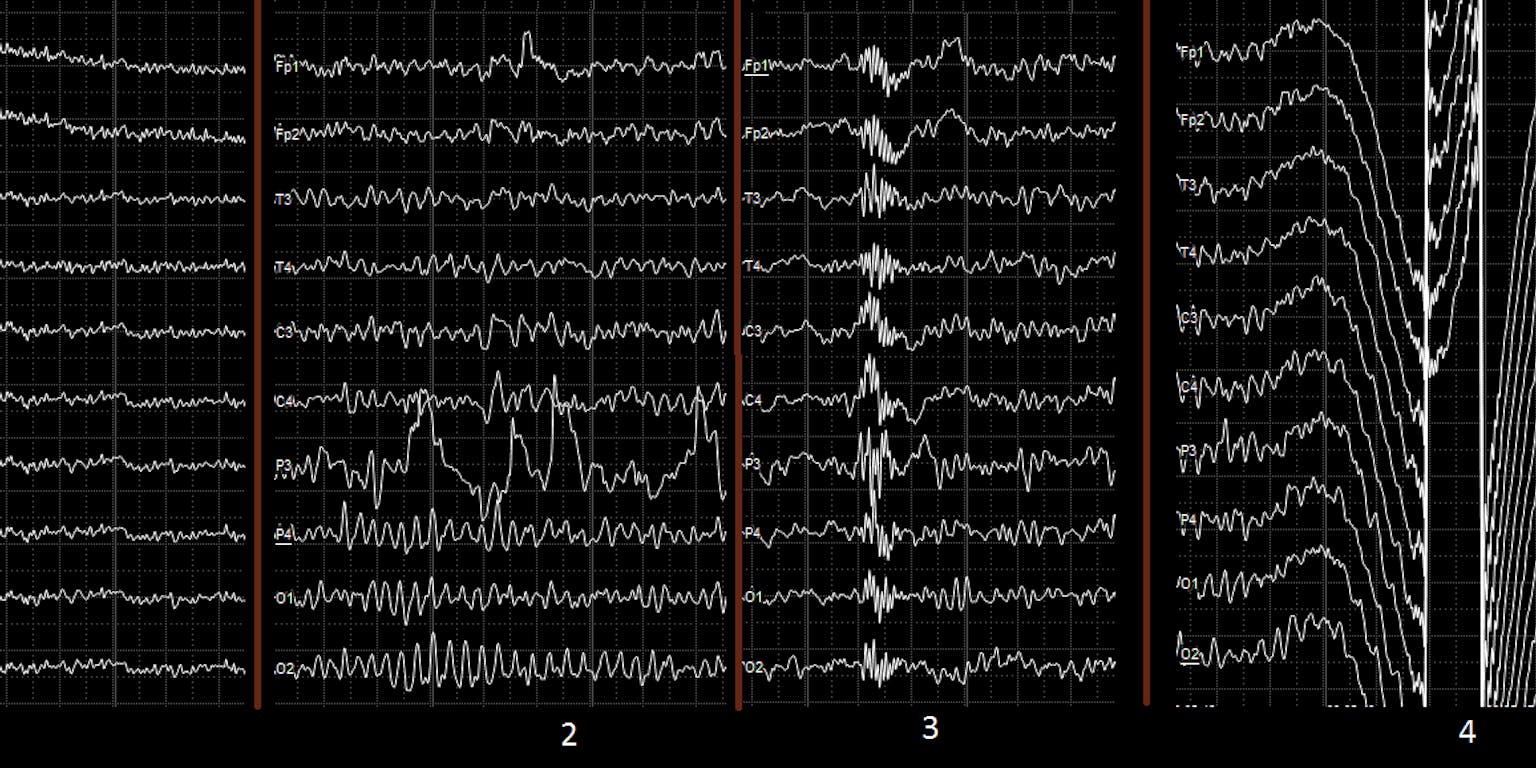

Hoewel we nog nauwelijks weten hoe hersenen bewustzijn ‘produceren’, is de moderne aanname, dat dit samenhangt met intensieve communicatie tussen relatief ver van elkaar verwijderde hersendelen. De onderzoekers maten daarom bij de patiënt – voor en na het begin van de stimulatie – op een groot aantal punten van diens schedel de elektrische signalen (het EEG). De samenhang tussen al die locale EEG’s is te vatten in een getal, de wSMI. (zie de afbeelding).

EEG van de vegetatieve patiënt voor (boven) en na (onder) het stimulatieprogramma. De kleurcode geeft de mate van de samenhang in activiteit aan tussen verschillende hersengebieden. Als hersengebiedjes los van elkaar ieder hun eigen ding doen, kan er geen sprake zijn van bewustzijn, is tegenwoordig het idee van neurologen.

Martina Corrazol, Current BiologyDe wSMI nam door de nervus vagus stimulatie significant toe, wat je zou kunnen opvatten als een objectieve maatstaf voor toegenomen bewustzijn. Ook de theta-golven in het EEG – met een frequentie van 4 tot 7 hertz – namen in kracht toe, wat eveneens wordt gezien als een indicator voor bewustzijn.